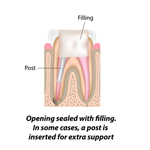

PERNI MONCONI ESTETICI

Con perno-moncone si intende una soluzione per sostituire la corona di un elemento dentario naturale trattato endodonticamente, mediante una doppia ritenzione meccanica: da una parte il perno, collocato e fissato all'interno di una radice e, dall'altra parte il moncone, sporgente dalla radice, in posizione coronale, crea un sostegno artificiale, in grado di garantire il fissaggio all'elemento da protesizzare.

Con questo metodo e' possibile restaurare i denti che hanno difetti estesi della corona ed e' una procedura che viene effettuata solo su dente devitalizzato.